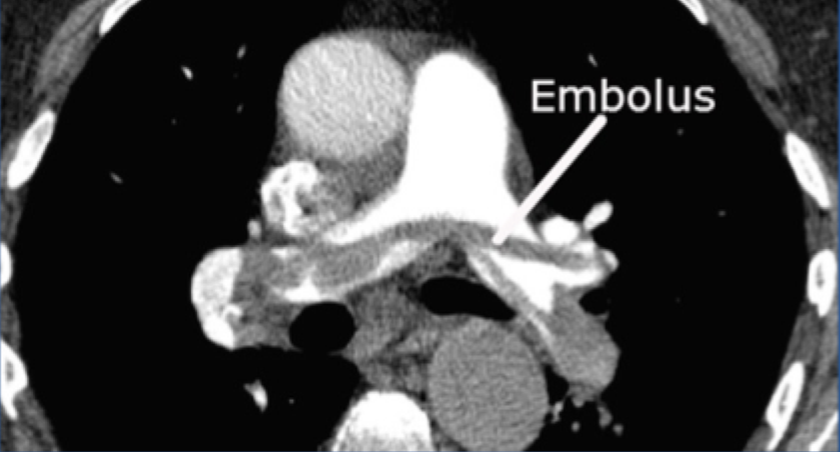

8

Q

?

A

spiral CT pulmonary angiography of PE